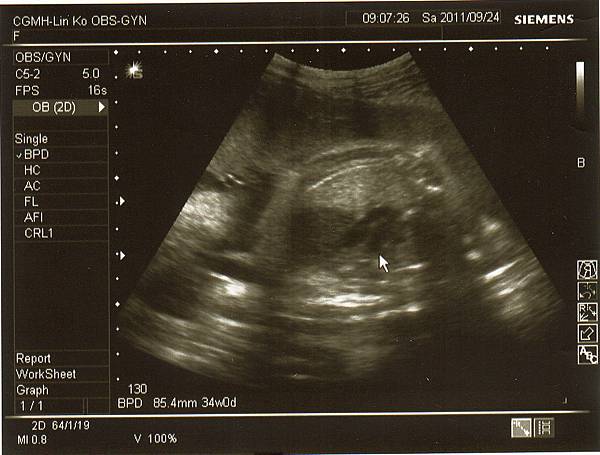

產檢結果兔妹妹目前約兩千多克,

醫生說很重要的兩條動脈~

兔妹妹的腎臟(不過我實在看不太懂)~